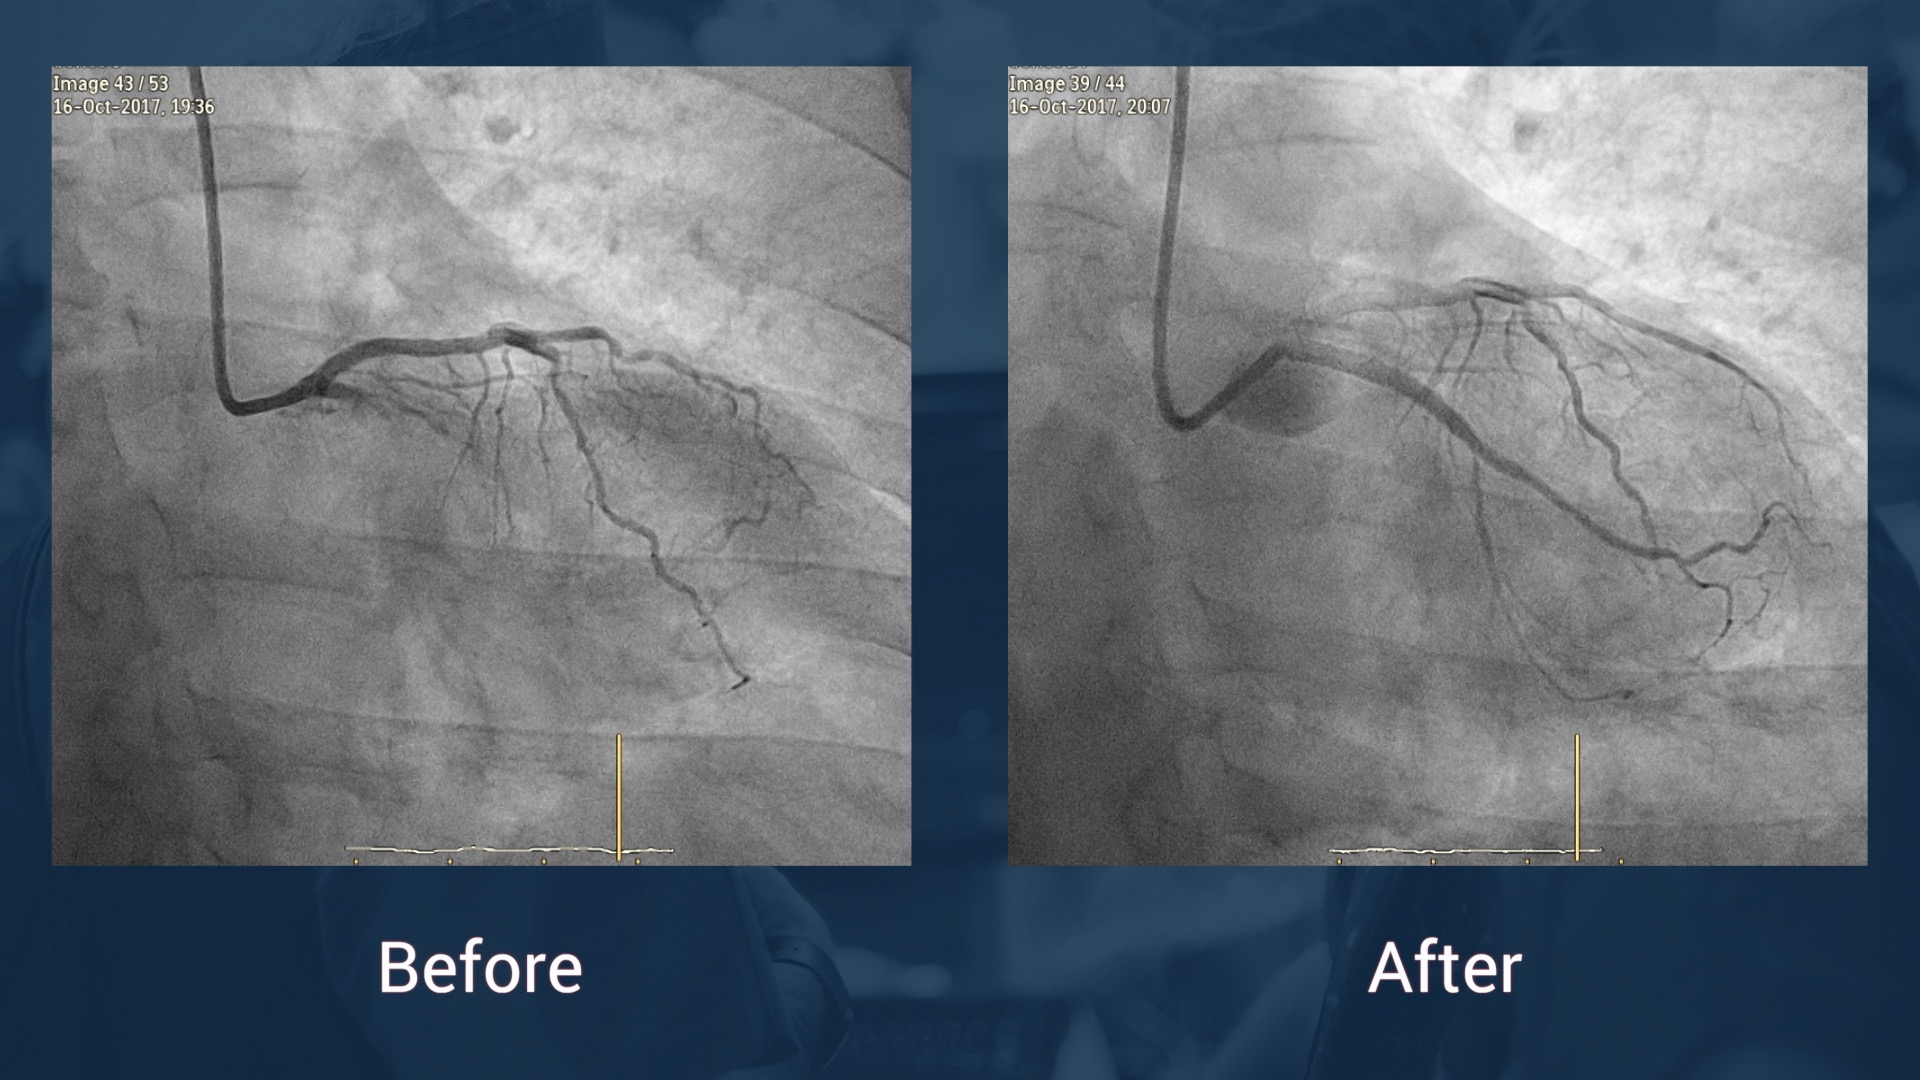

Chronic occlusions, what else? Discover New Tools in coronary and peripheral diseases

Anchoring catheter, microcatheter, dual lumen or extension catheters?